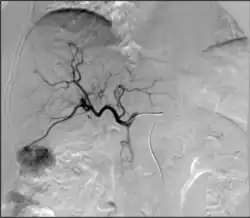

1. Angiography: Sometimes referred to as traditional angiography, catheter angiography or digital subtraction angiography (DSA). A small needle is inserted into a blood vessel, then exchanged for a catheter over a wire. The catheter is directed at the vessel to be studied, and contrast is directly injected to evaluate the lumen under video X-ray. This is an older technique than modern CT angiography or MR angiography, but provides unique advantages. With a catheter in place, provocative maneuvers can be performed such as breath holds or instillation of vasodilators, to evaluate a patient's blood flow dynamically. This can reproduce symptoms and identify functional abnormalities in a vessel that a static CT or MR imaging cannot.[80][81] Angiography provides the basis for all endovascular therapy.

2. Balloon angiography: The foundational IR procedure. Small balloons can be inflated inside a narrowed vessel to open it. These can then be safely deflated and removed. Some balloons have a specialized surface material, such as fine razor blades ("cutting balloons") to crack the plaque or instill a coating of medicine ("drug-coated balloon") that keeps the vessel open longer.